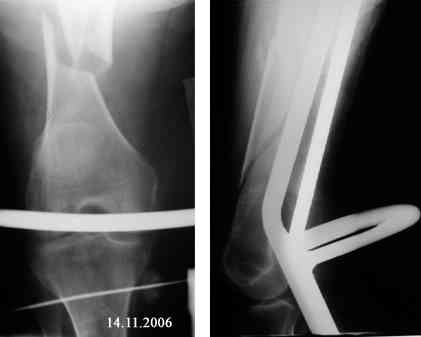

В продолжение темы оскольчатого перелома бедренной кости.

Р-граммы в динамике

Уважаемый Александр! Спасибо за предложение по устройству больной. Каким образом вы могли бы помочь я не вижу. Больная из г. Евпатории Крым, Украина, как я уже писал неимущая. В нашем отделении такие операции не делаются (хотя есть ЭОП - единственный в Крыму). Заведующий на оперативное лечение больной почему-то не настроен. По-моему несращение ей обеспечено, завтра зайду к ней - проверю (52 дня на вытяжении!). Вопрос - что с ней делать дальше если на операцию не идут? Выгнать с ложным суставом домой умирать? Или лежать до самой смерти (близкой) на вытяжении - я понимаю - человек ко всему привыкает но не до такой же степени. Кстати - сопутствующее у нее сросшийся чрезнадмыщелковый перелом левой плечевой кости (травма и операция (открытая репозиция, МОС спицами) в мае 2006 года).